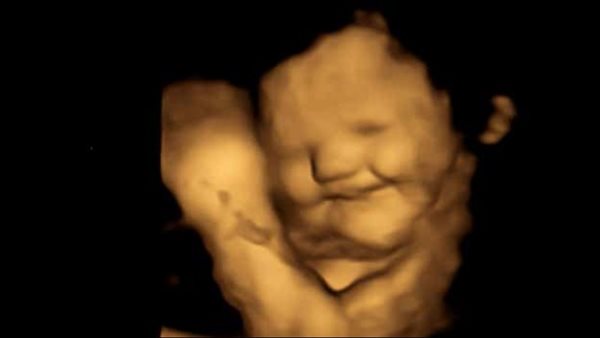

أجرى باحثون من جامعة دورهام فحوصات بالموجات فوق الصوتية رباعية الأبعاد لـ 100 امرأة حامل لدراسة كيفية تفاعل الأجنة بعد تعرضهم للنكهات من الأطعمة التي تناولتها أمهاتهم.

وأظهرت الفحوصات، أن الأجنة التي تعرضت للجزر كانوا يبتسمون، ويرى الباحثون أن ما تأكله الأمهات طوال فترة الحمل يمكن أن يؤثر على تفضيلات الذوق لدى أطفالهن بعد الولادة، وقد يكون له آثار على عادات الأكل الصحية.

وشملت الدراسة، فحص الأمهات في الأسبوع 32 و36 من الحمل، وذلك لمعرفة ردود فعل وجه الجنين على نكهات اللفت والجزر، وتم إعطاؤهم كبسولة واحدة تحتوي على ما يقرب من 400 مجم من الجزر أو 400 مجم من مسحوق الكرنب، وأظهرت الدراسة تفاعل الأطفال بصور إيجابية عند تناول أمهاتهم للجزر والكرنب.